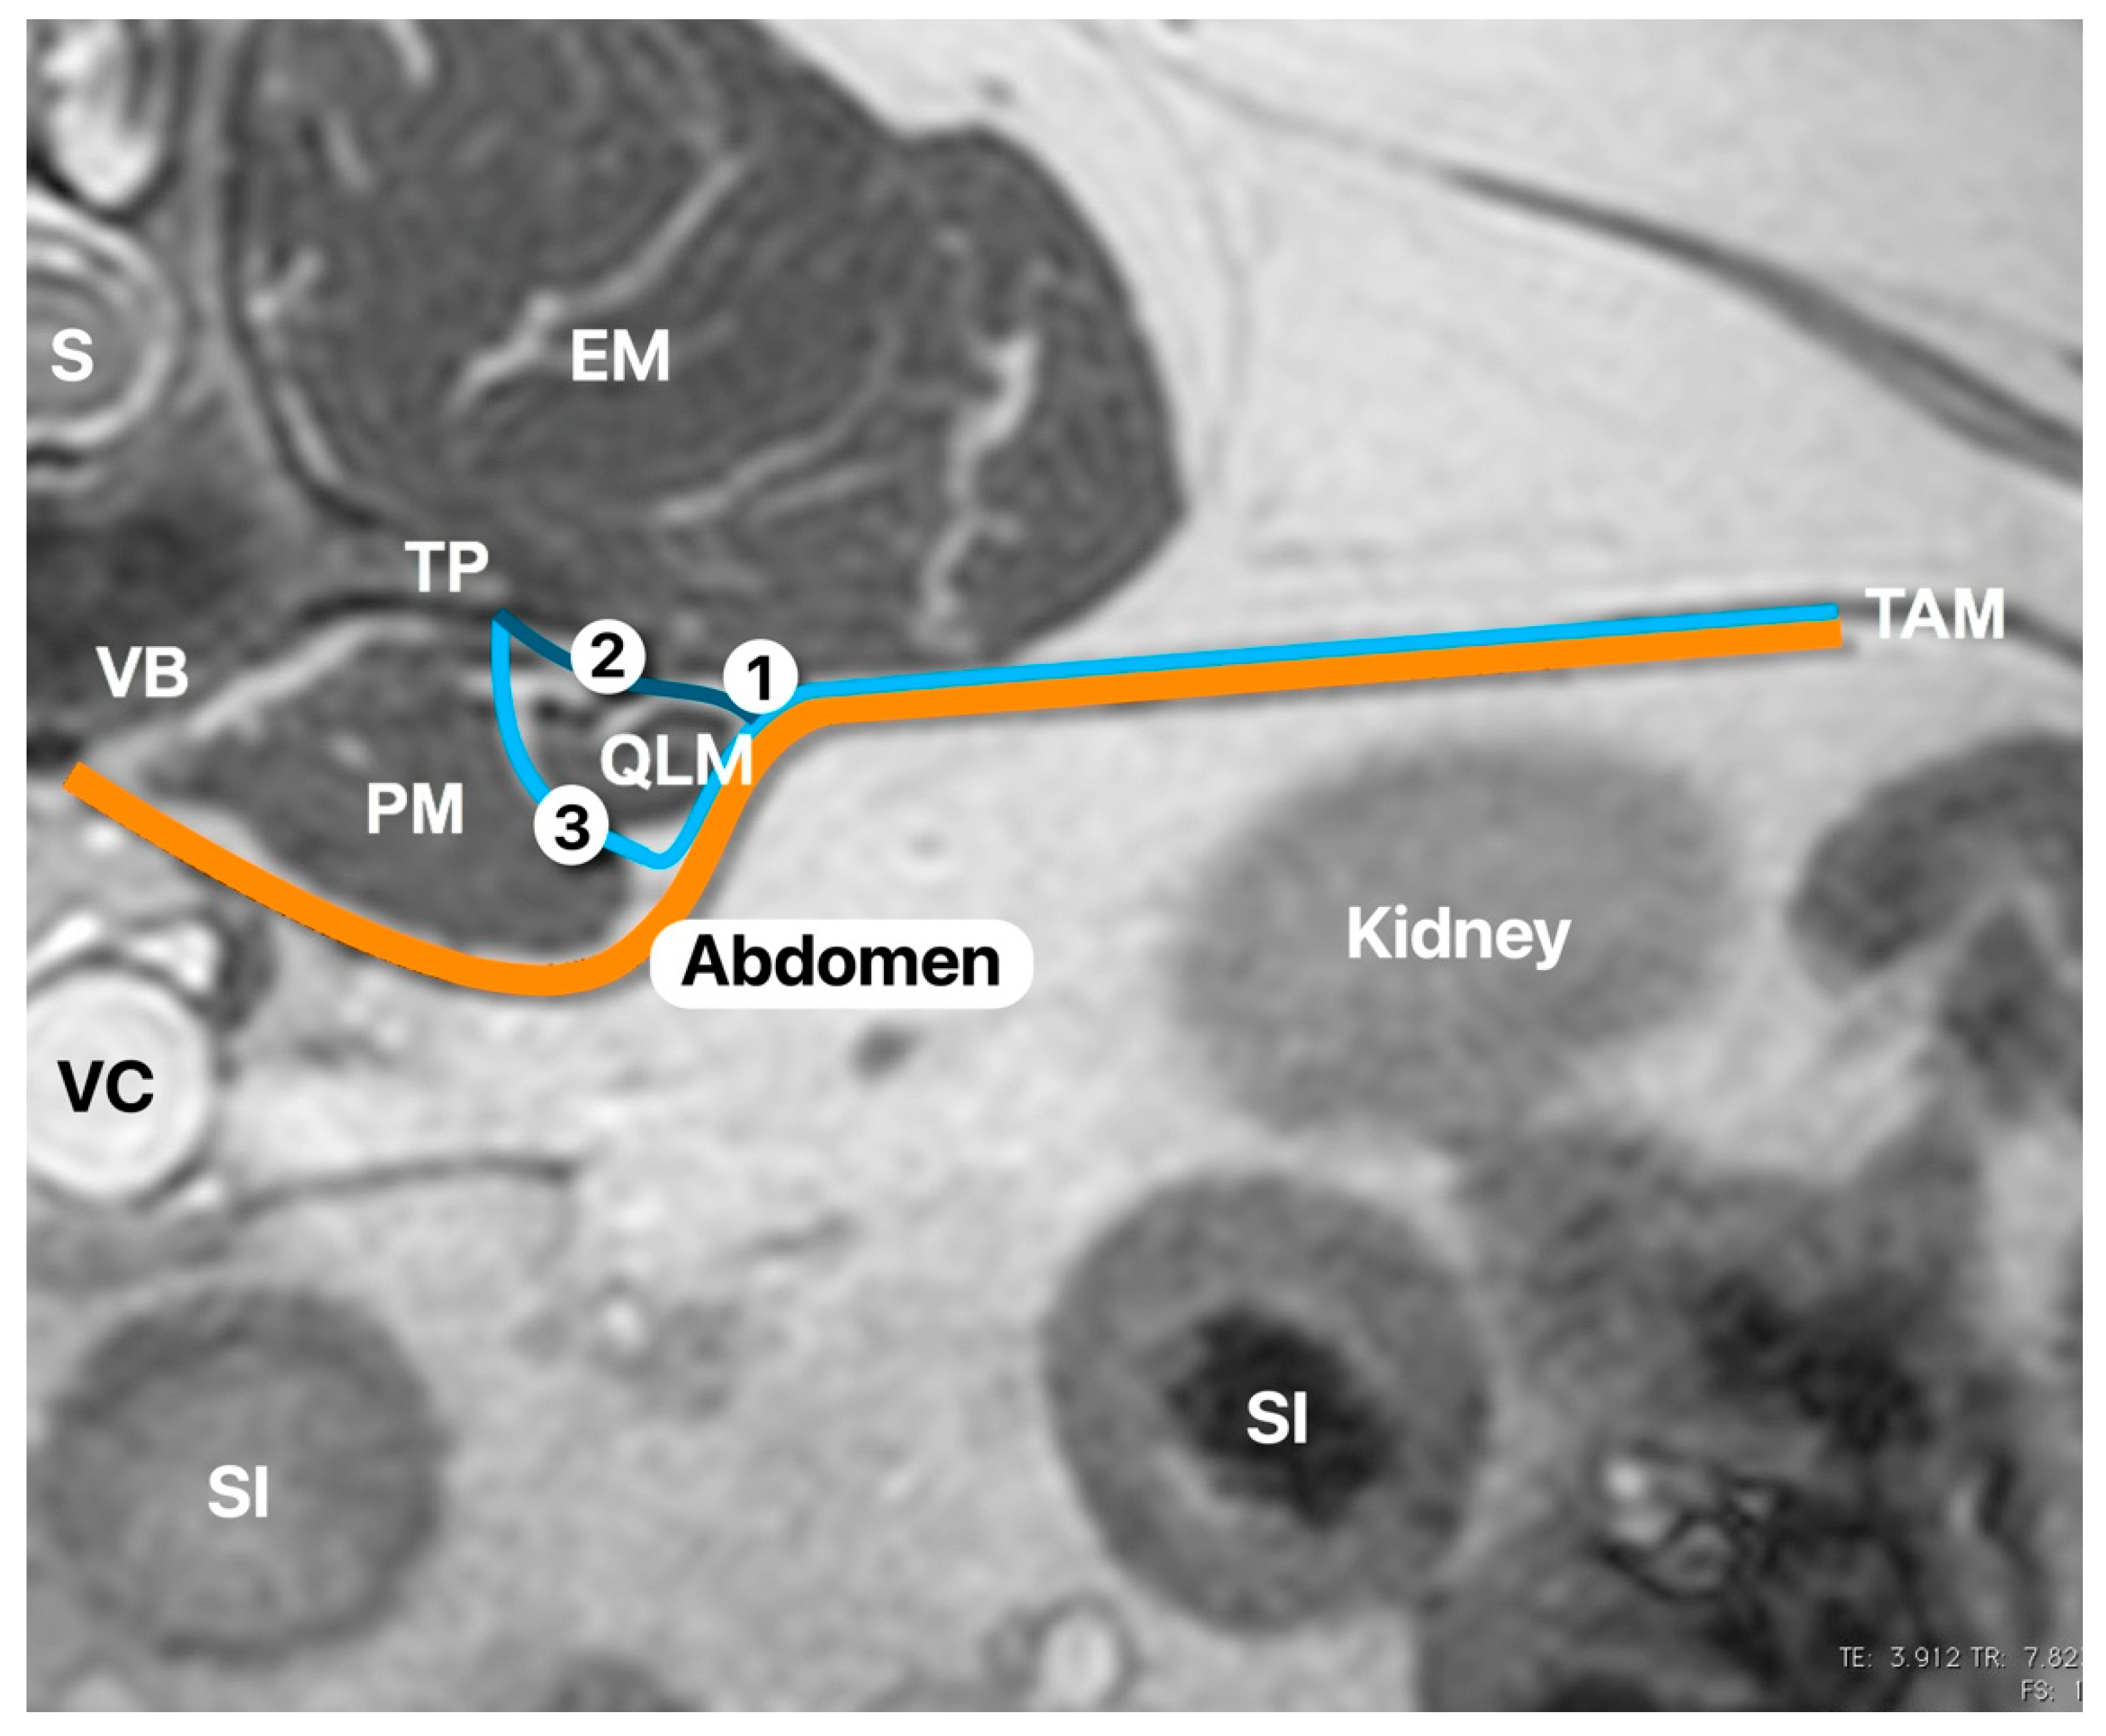

Figure 1. Transverse view of a canine abdominal MRI at the level of the first lumbar vertebrae (L1) to illustrate the anatomy. The picture shows the relevant anatomy related to the quadratus lumborum block (QLB) and the different approaches described in the human literature to perform the QLB. PM, psoas muscle; QLM, quadratus lumborum muscle; TP, transverse process; VB, vertebral body; S, spine; EM, epaxial muscles; TAM, transversus abdominis muscle; VC, vena cava; SI, small intestine. The orange line is the fascia transversalis. The light blue line is the anterior thoracolumbar fascia. The dark blue line is the middle thoracolumbar fascia (based on three-layered model of the thoracolumbar fascia [7]). (1) Point of injection of the QLB1 technique; (2) point of injection of the QLB2 technique; (3) point of injection of the QL3 technique. Picture was taken and modified by the author without any copyright dispute.

The US-guided QLB technique was performed in the following manner. The US probe was placed in a transverse plane over the lumbar muscles just caudal to the last rib using a paramedian sagittal oblique (subcostal) approach described by Elsharkawy [13] in humans. Once in position, the probe was rotated slightly cranial to visualise the following anatomical structures: quadratus lumborum muscle, psoas muscle, lateral aspect of the body of the first lumbar vertebrae, and the transverse process of the first lumbar vertebrae (Figure 1). The needle was inserted in-plane and advanced at a 45º angle from dorsolateral to ventromedial until its tip was placed between the quadratus lumborum and psoas muscles (Figure 2). At this location, the mixture was injected into the fascial plane. A volume of less than 1 mL of saline was first injected to confirm the correct position of the tip of the needle. The injection was considered as correct when hydrodissection of the quadratus and psoas muscles together with the ventral movement of the thoracolumbar fascia was noted (Figure 3). If this pattern was not visualised, the needle was redirected until this hydrodissection was observed.

The pattern of distribution (linear +/− lateralised) found in our study could be related to the injection point. This is compatible with the different approaches described in human anaesthesia [16,17]. The QLB1 (or lateral approach) involves administering the local anaesthetic inside the triangle formed by the lateral aspect of the QL muscle, internal aspect of the transversus abdominins muscle, and the anterior thoracolumbar fascia. This approach will produce a lateral distribution of the local anaesthetic. With the QLB2 (or posterior approach), the needle is aimed at the dorsal aspect of the QL muscle, and local anaesthetic is administered inside the middle thoracolumbar fascia. This approach will produce a linear distribution dorsal to the QL muscle. The QLB3 (or transmuscular approach) inserts a needle through the quadratus lumborum and injects local anaesthetic between QL and the psoas muscles. This approach will separate both muscles and will produce a linear and slightly lateral distribution since the anterior thoracolumbar fascia is in direct contact with the ventral border of both muscles [16,18]. Finally, the QL intramuscular approach involves advancing the needle tip until it penetrates the fascia and it is then inserted into the QL muscle [2]. In our study, the QLB3 was utilised in all the cases, and CT images showed a linear and slightly lateral distribution pattern compatible with the QLB3 approach. It is still unclear as to which approach would be more advantageous regarding the authors’ knowledge based on the human literature. There might be some clinical differences since the QLB3 approach appears to spread more caudally but less cranially than the other approaches [2]. Garbin et al. [10,11] found more cranial spreading using a QLB1 versus QLB3 approach in their studies in dogs. However, clinical studies are needed in veterinary medicine to confirm these results.